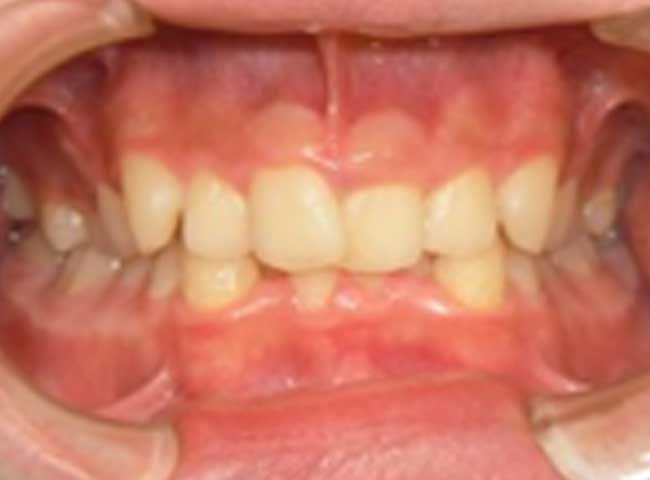

よくあるお悩みの例

CASE